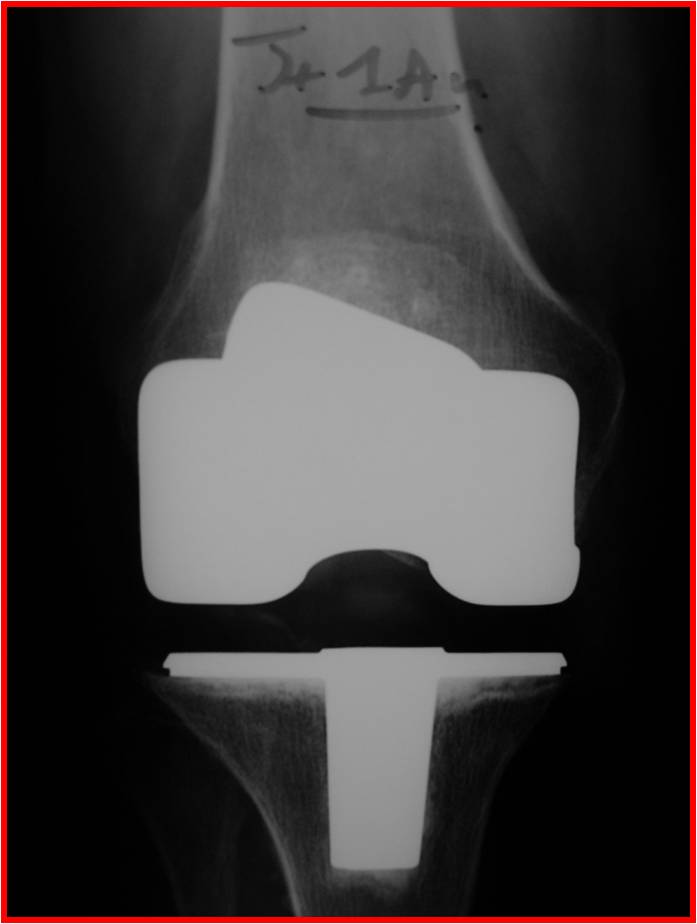

Il s’agit d’une intervention chirurgicale ou les surfaces articulaires usées du fémur et du tibia sont remplacées par des implants métalliques, avec un plastique (Poly-éthylène – PE) entre les 2. La rotule est en général remplacée elle-aussi par un implant en PE.

Il existe des nombreux types d’implants: prothèses totales (semi contraintes ou à charnières) ou prothèses uni-compartimentales internes ou externes, et l’on adapte le type de prothèse au patient.

La prothèse totale de genou : PTG

La PTG remplace les 3 surfaces articulaires fémoro-tibiales interne et externe, et fémoro-patellaire (la rotule).